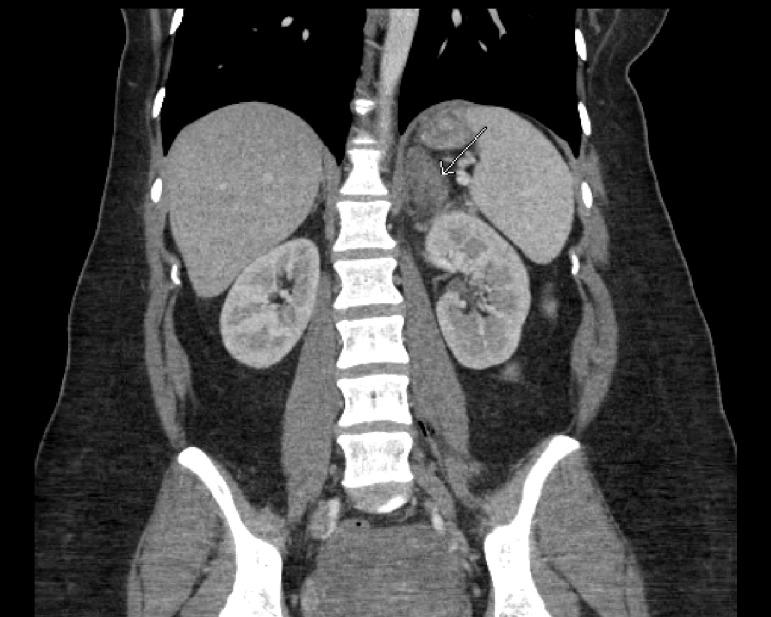

Spontaneous adrenal hemorrhage (SAH) is a serious medical condition associated with variable clinical presentation depending on the extent of the hemorrhage. Pregnancy-induced adrenal hemorrhage is poorly understood. A low cortisol level in the peripartum period with radiological findings is sufficient to establish the diagnosis. Prompt hormone replacement and supportive care to ensure good clinical outcomes is crucial. Due to the potentially life-threatening complications, physicians should have a high suspicion for adrenal hemorrhage when they evaluate patients with hypotension, fatigue, and abdominal pain during the peripartum period.

自发性肾上腺出血(SAH)是一种严重的医学病症,其临床表现因出血程度而异。妊娠引起的肾上腺出血目前了解甚少。围产期皮质醇水平低并伴有影像学检查结果足以确诊。及时进行激素替代和支持治疗以确保良好的临床结局至关重要。由于存在潜在的危及生命的并发症,医生在评估围产期出现低血压、疲劳和腹痛的患者时,应高度怀疑肾上腺出血。